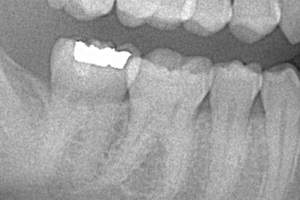

また、銀歯が入っていると、レントゲンにも真っ白にうつってしまいますので、発見がどうしても遅れがちに

なります。

銀歯を詰めた口内のレントゲン写真